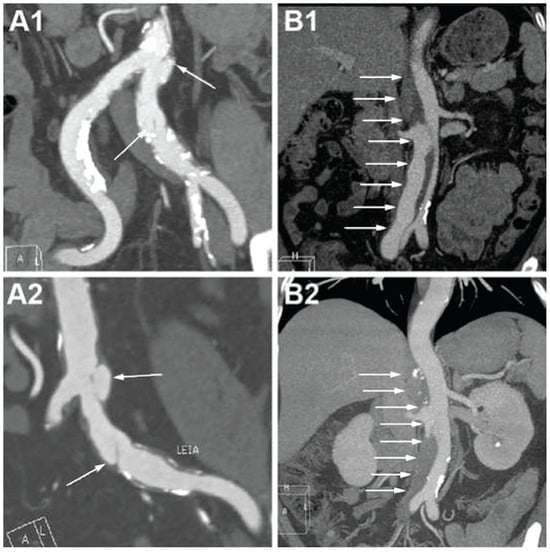

4.2. CTA Imaging Findings